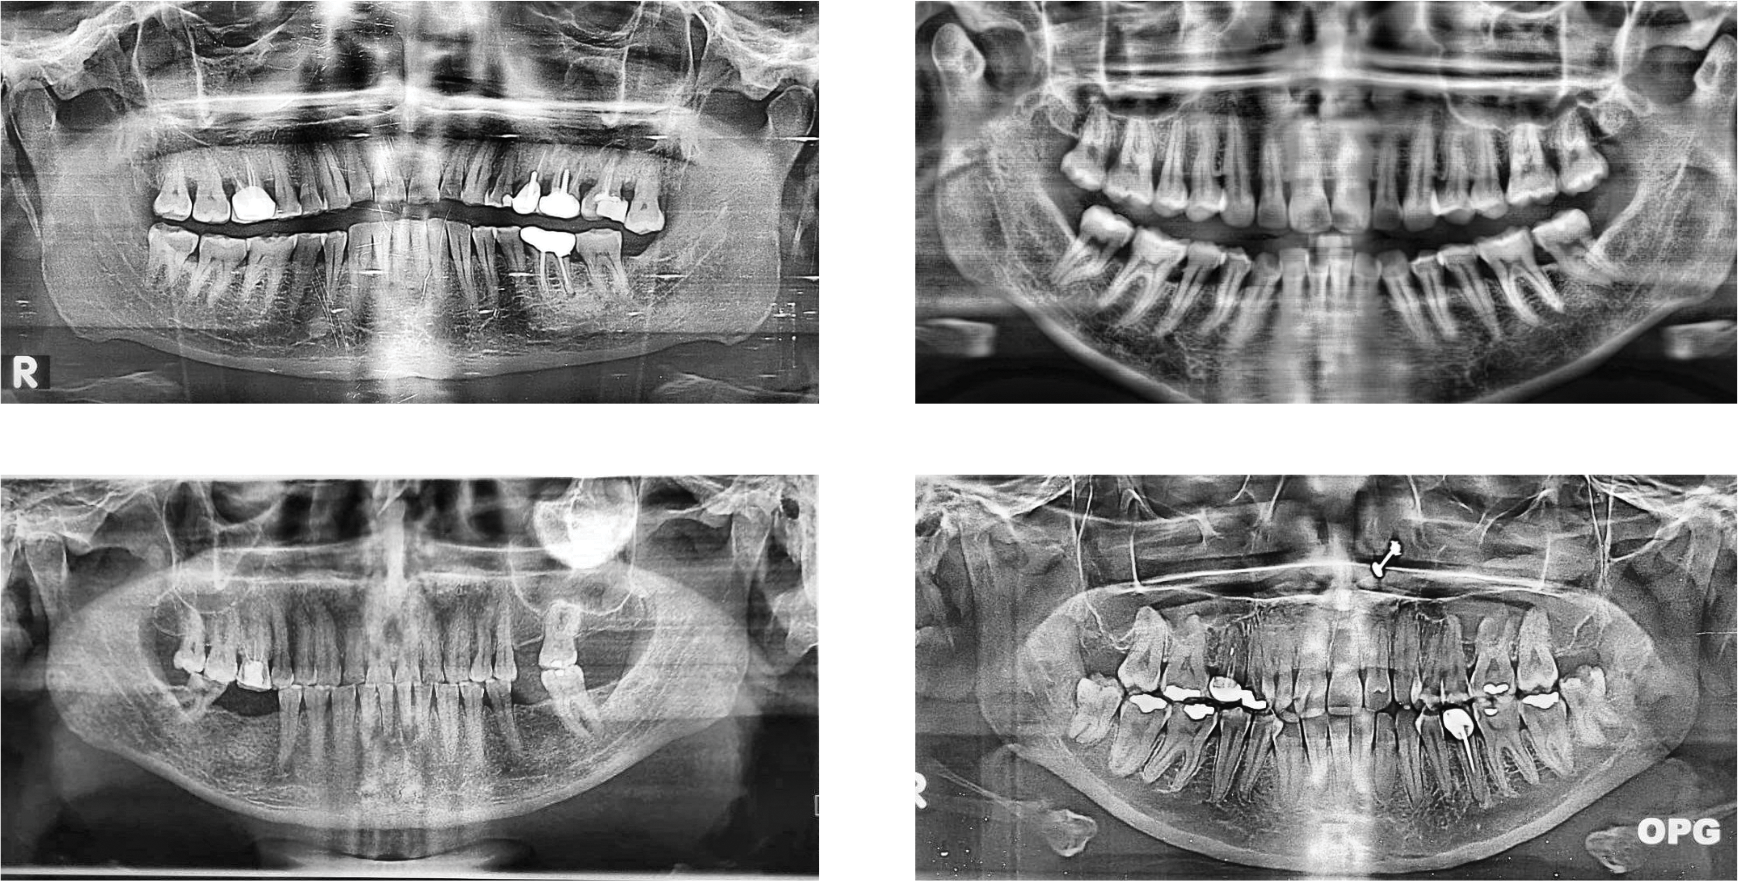

The primary dataset employed in this research is the publicly accessible “Dental OPG X-RAY Dataset” [42]. This resource was specifically curated to support deep-learning research in the detection and classification of dental diseases from panoramic radiographs. The original collection consists of 232 OPGs. The OPG images were initially captured by photographing X-ray films with a 64-megapixel Samsung A52 smartphone camera to ensure clarity and detail, as shown in Fig. 2. Prior to processing for this study, the dataset creators enhanced the images using Contrast-Limited Adaptive Histogram Equalization (CLAHE) to improve the visibility of dental structures.

Figure 2: Examples of panoramic dental radiographs (OPG) from the dataset

The dataset deliberately excluded individuals under 10 years of age. As stated in the dataset’s description, this targeted selection was made to focus on adult dental structures, which exhibit significant anatomical and pathological variations compared to those of children. The severe class imbalance, particularly for ’Fractured Teeth,’ with only 13 instances. This low count is reflective of the inherently lower prevalence of fractured teeth compared to other dental conditions in typical clinical populations, as captured in this [42] dataset.